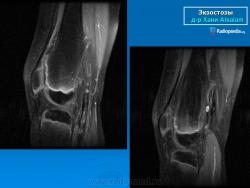

Локализация остеохондромы: частота поражения отдельных костей различна; нижний коней бедренной кости, верхние отделы плечевой и большеберцовой костей поражаются более чем у половины больных. На всем протяжении остеохондрома покрыта надкостницей. Она может быть обнаружена и в других костях, за исключением костей лицевого черепа. Все же поражение костей позвоночника, кистей рук и стоп встречается редко. При рентгенологическом исследовании видна типичная картина узкого или широкого выроста вблизи эпифизарной части пораженной кости. Обычно плотность узла неоднородная, имеются многочисленные плотные участки, соответствующие обызвествленным хрящевым долькам. Хрящевая «шапочка» большей частью не определяется, поскольку хрящ остается необызвествленным. Она может быть выявлена только при магнитно-резонансной томографии.